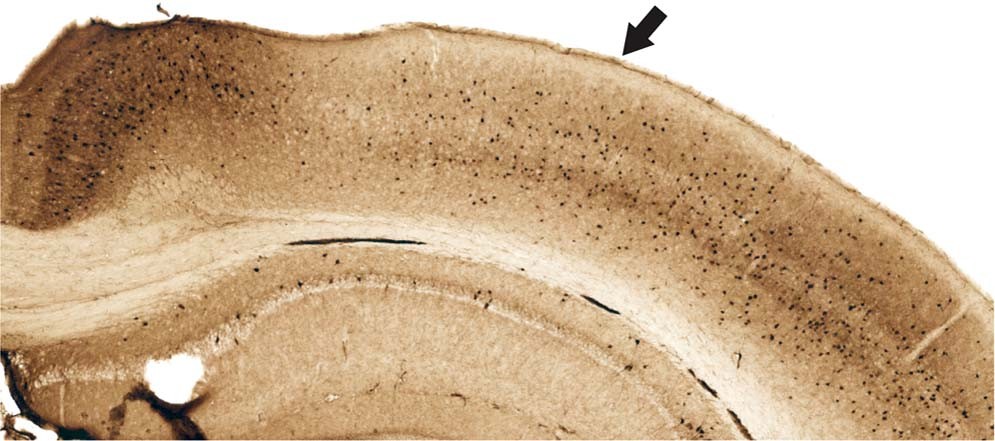

Figure 2

Parvalbumin stained tissue for region of interest analyses. Example of facilitated identification of a region of interest, parietal cortex, using adjacent parvalbumin stained tissue. Parietal cortex (arrow) can be readily identified by the emergence of layer IV (medial boundary) and ending at the lateral border where parvalbumin staining becomes more robust.